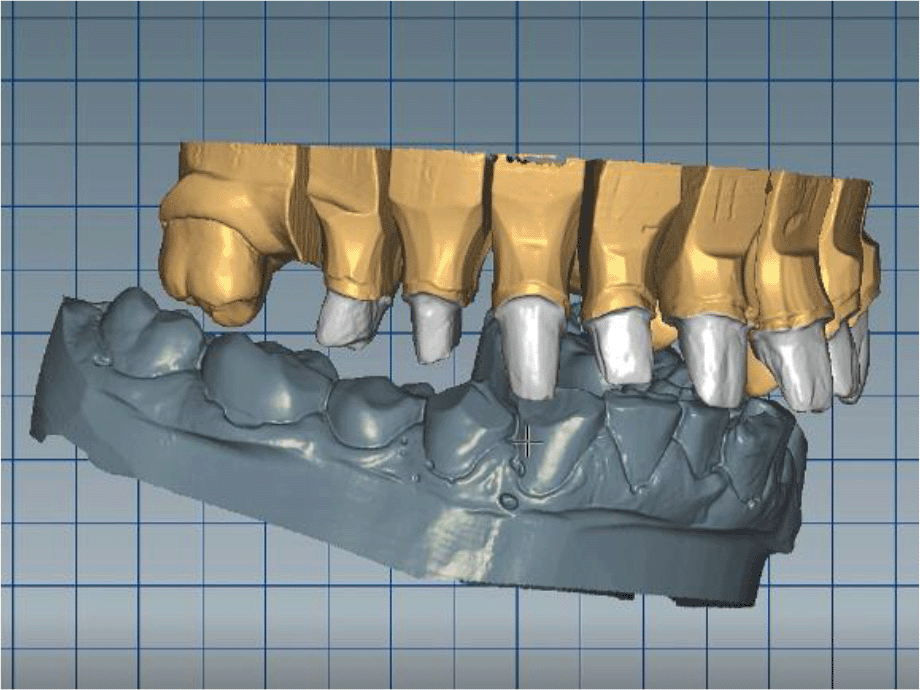

The cast gypsum models were scanned with a laboratory scanner and the obtained digital models were subjected to additional processing. Briefly, transfer of the morphological planning for the upper dentition (crown strategy) and for the lower dentition (digital wax up strategy, pontics) was performed (Figures 9 and 10).

26dd931c-41d3-478d-bec1-8cb211d0a4b8_figure9.gif

Figure 9. Clinical situation after upper preparation with increased VDO.

26dd931c-41d3-478d-bec1-8cb211d0a4b8_figure10.gif

Figure 10. Digital design on both jaws.